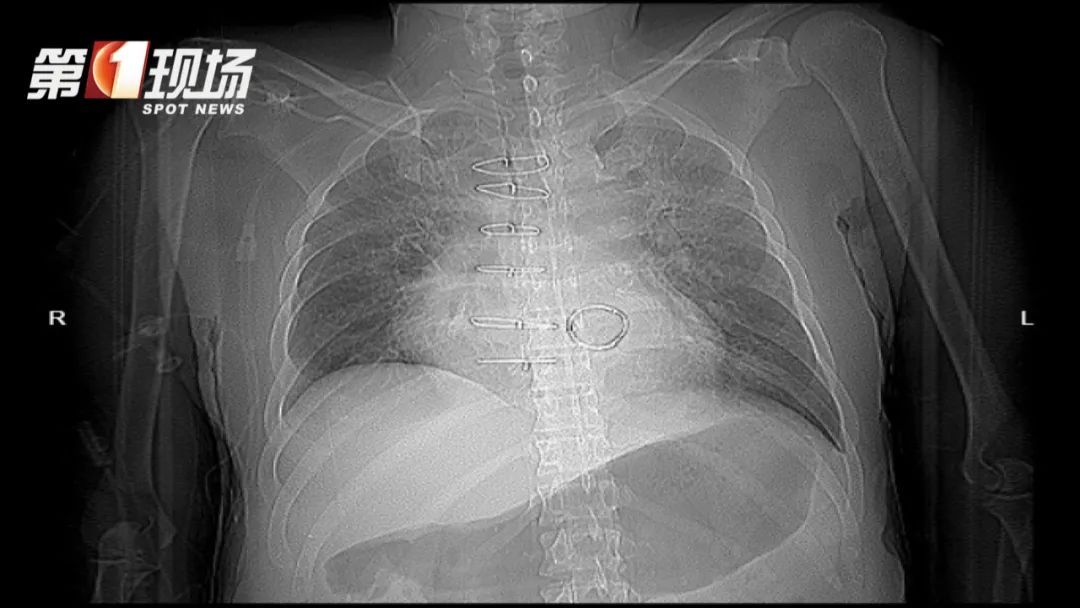

一年前,刘先生在中大八院接受了换瓣手术,长期依赖肾透析维持生命。然而就在一个月前,细菌再次感染他的心脏瓣膜,导致心脏衰竭、肝功能衰竭、呼吸衰竭和感染性休克,生命垂危。

只有尽快再次接受换心脏瓣膜手术,刘先生才有可能挺过这一难关。然而,危重的病情,让他的身体可能经不住第二次心脏手术。

他心脏和周围的组织都粘在一起,一塌糊涂。要一点一点像“挖地雷”一样把这个清理干净,才能看出心脏的结构,然后再把去年做的瓣膜给重新换掉,从技术上比较困难。

如果不通过手术改善情况,刘先生的生命恐怕只剩下一两周的时间。好在经过9小时的紧张手术,医生成功为他置换了两个瓣膜。